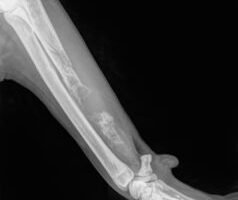

Osteosarcoma en perros: una neoplasia aterradora